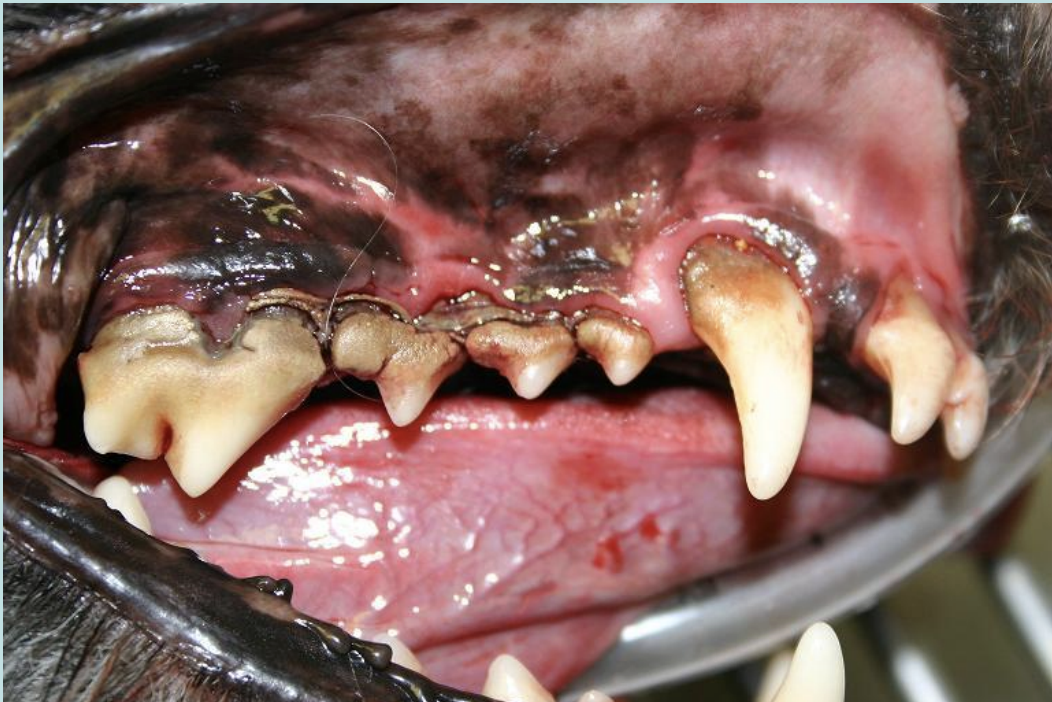

Oral Neoplasia

rapidly growing tumor

dome shaped and may be black, brown, mottled, or unpigmented

Malignant melanoma-most common type in dogs

Squamous cell carcinoma-most common type in cats